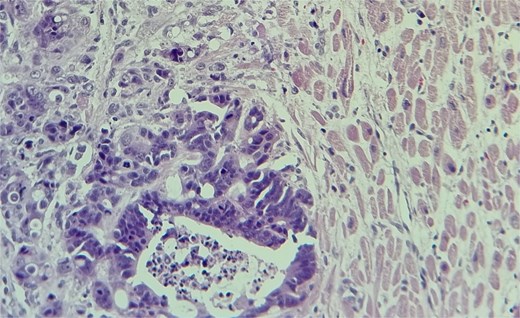

Subsequent echocardiography showed an ejection fraction of 70%, normal left ventricle dimensions, grade II left ventricular diastolic dysfunction, and a mass attached to the right ventricular wall. Mild pulmonary hypertension was noted. The patient underwent an open-heart procedure via median sternotomy under cardiopulmonary bypass. The tumor was adherent to the right ventricular wall, necessitating meticulous dissection to preserve myocardial integrity. The mass was excised completely, and histopathological examination confirmed metastatic adenocarcinoma consistent with a colon primary (Figs 4 and 5). Postoperatively, the patient initially showed stable cardiac function with preserved ejection fraction.

The metastatic tumor cells form glandular structures and infiltrate the myocardial tissue in a disorganized manner.